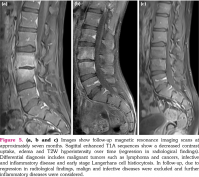

The patient was placed on steroid therapy, and a good response was achieved in terms of clinical and laboratory findings. Figures 1 and 5 present the MRI findings at baseline and during follow-up. Thus, early diagnosis provided good response to disease without organ damage.